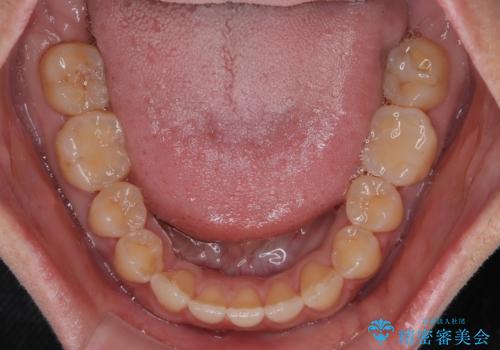

- 極端な開咬を気にして来院された患者様です。

開咬の方の特徴として、幼少期の指しゃぶりの癖や、強い舌の突出癖が挙げられます。

こちらの患者様も強い舌の突出癖が認められたため、矯正治療を行うにあたり、舌のトレーニングをしっかりと行っていただくように指示をいたしました。

開咬はインビザラインが得意とする歯列不正であるため、舌のトレーニングを行いながら、インビザラインにて矯正治療を行うこととしました。

担当医としては、もっと上下の前歯を接触させるところまで治療を進めたいという思いがありますが、今まで咀嚼できなかったものが食べられるようになったということで、この状態で治療終了となりました。